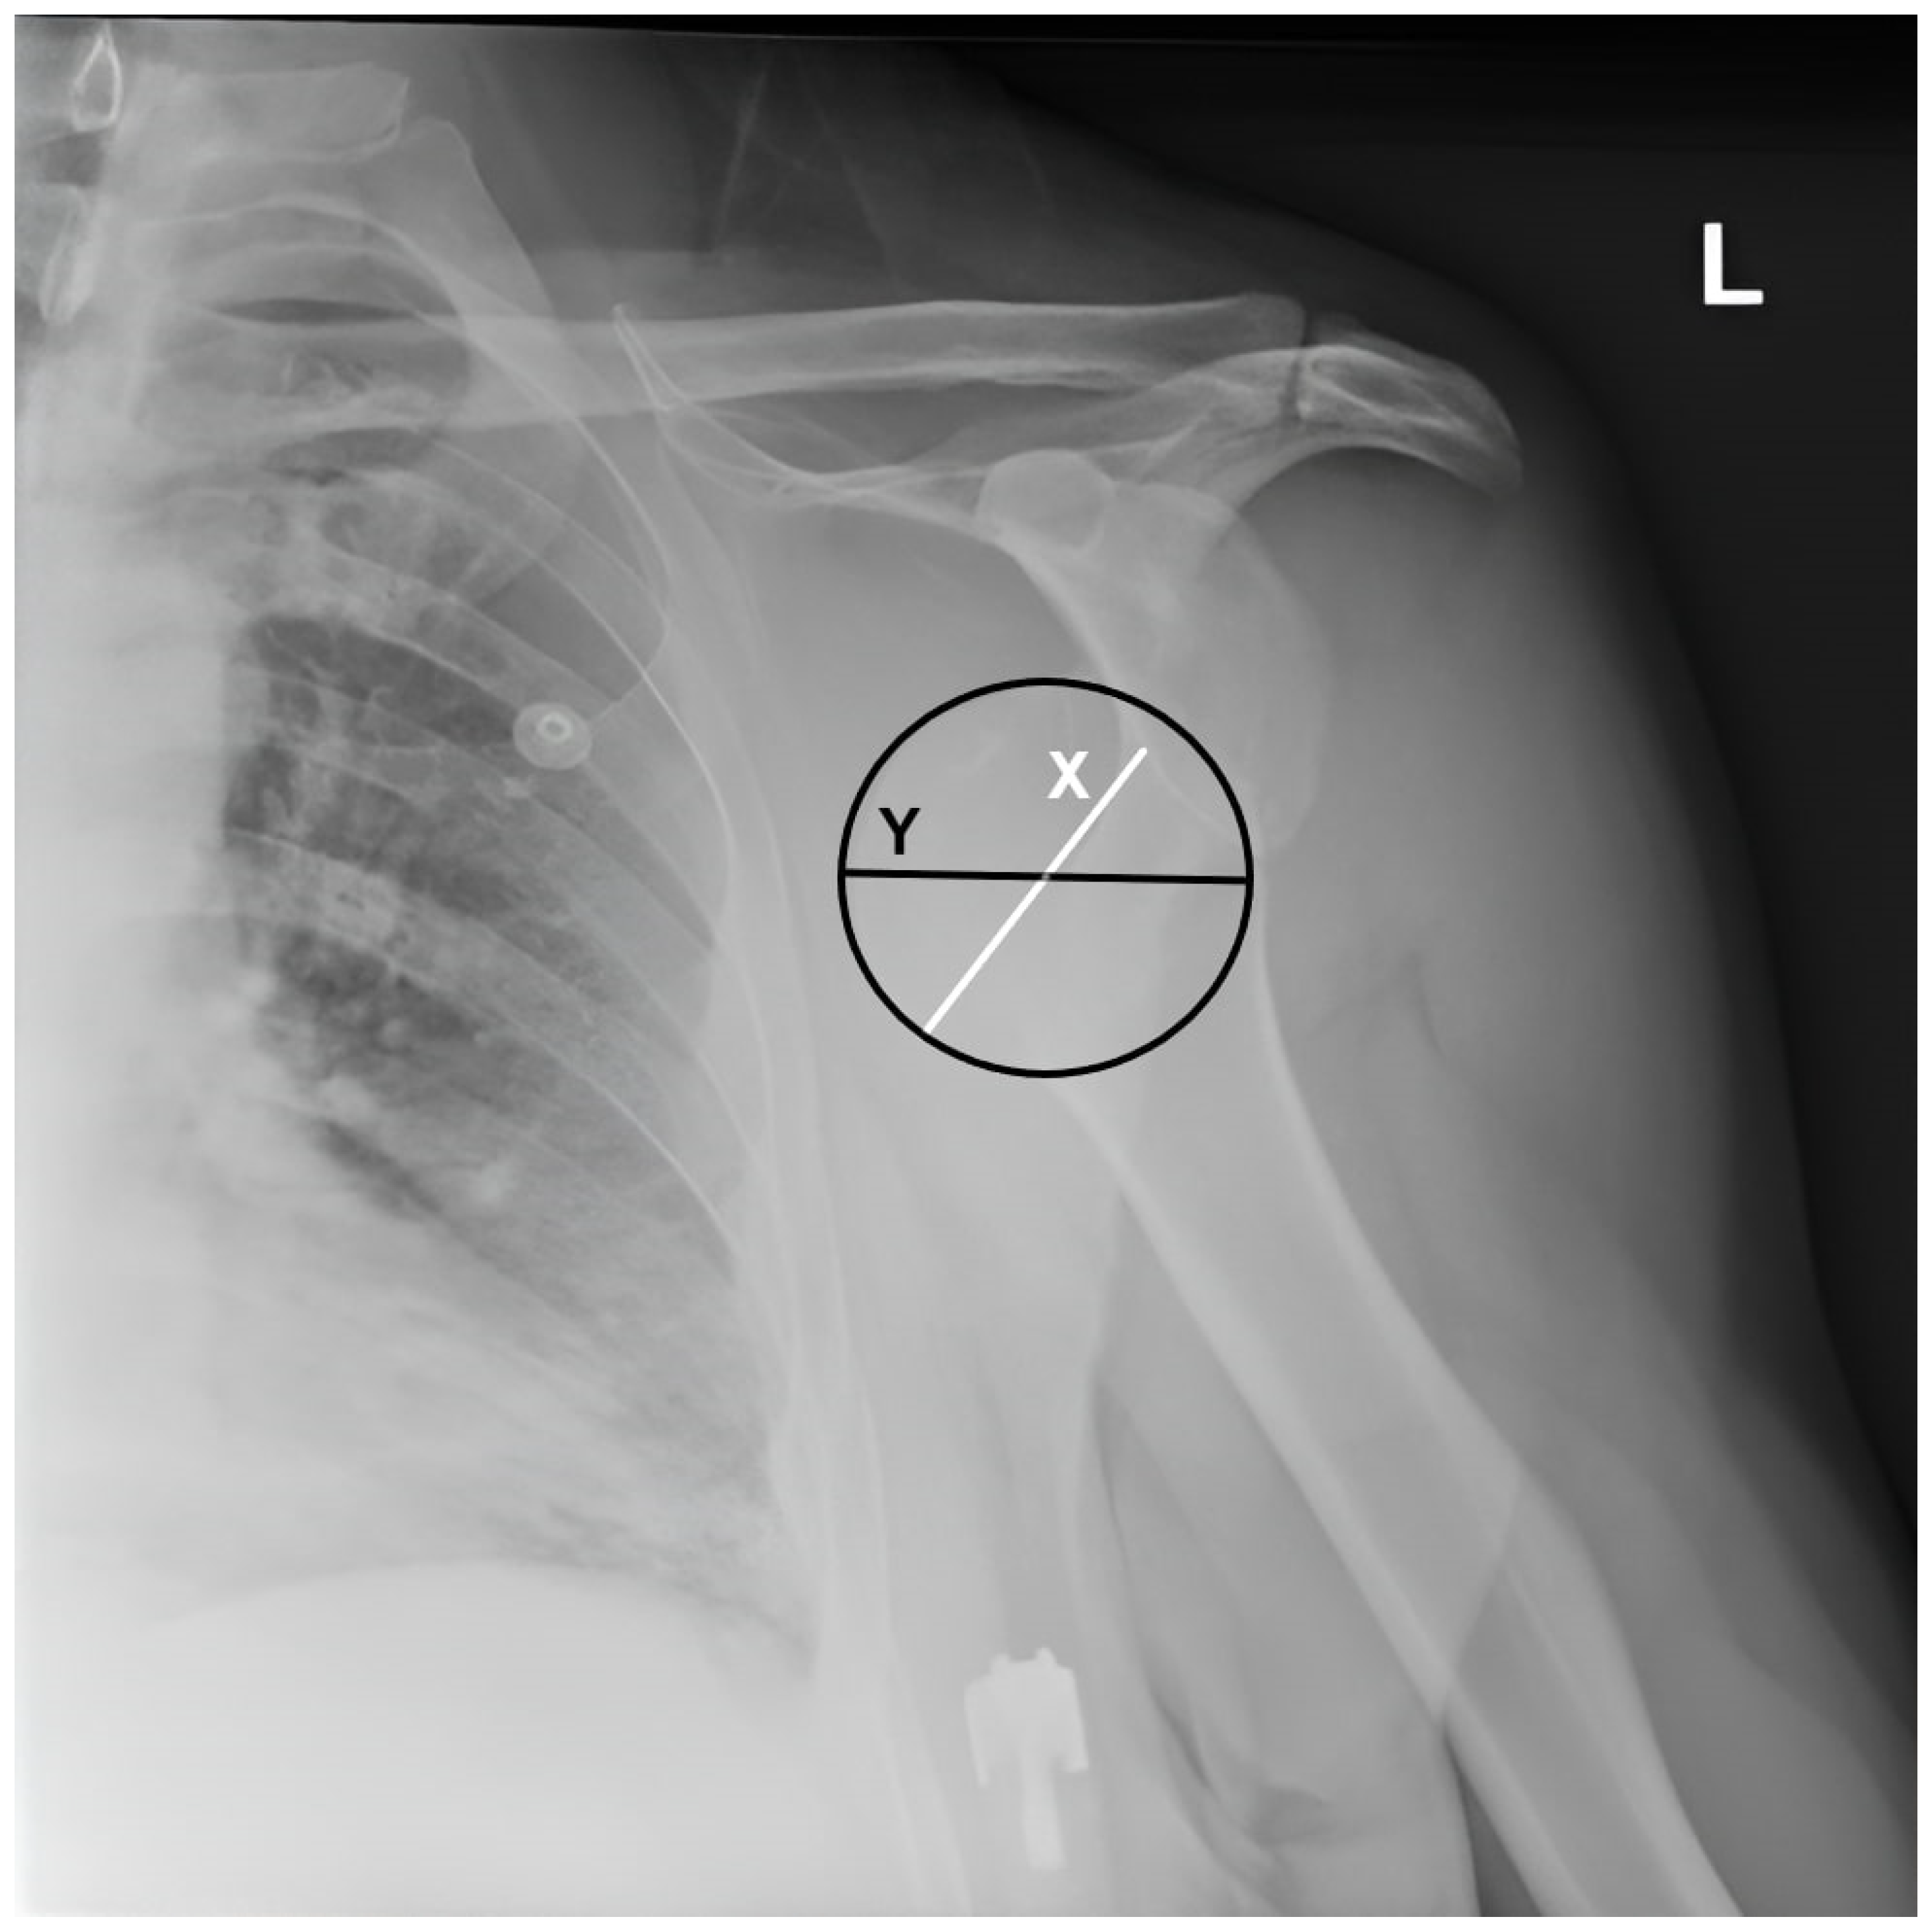

The humeral head position relative to the glenoid in the dislocated position was evaluated, and the ‘humeral head displacement ratio’ was calculated as the distance between the medial border of the humeral head and the anterior glenoid rim divided by the diameter of the humeral head on AP radiographs before reduction (Figure 2).

Figure 2. Measurement of humeral head displacement ratio. The humeral head displacement ratio is calculated as the distance between the medial border of the humeral head and the anterior glenoid (X) border divided by the humeral head diameter (Y) and multiplied by 100, L: Left.